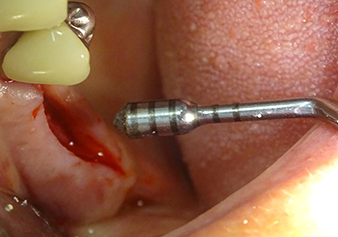

Implant bed preparation and augmentation

Following an intermediate check (Fig. 4) a further preparation step was performed (Fig. 5). Afterwards, the hydraulic Z35P instrument was used to lift the membrane to the desired position (Fig. 6 and 7). This was followed by further piezosurgical preparation of the implant bed, concluded with a rotary bur and shoulder milling cutter up to the implant diameter of 4.8 mm. Before the implant was inserted, the augmentation material (particle size approx. 0.8-1.6 mm) was introduced underneath the Schneiderian membrane (Fig. 8).

The implant bed is widened to 3.0 mm with the I3A instrument

Fig.5: In the next step, the implant bed is widened to 3.0 mm with the I3A instrument (power 100%, coolant 80%). The depth marks reliably prevent the preparation from going too deep.

The Schneiderian membrane is stretched 1.5-2 mm above the bony access

Fig.4: Intermediate check: The bone height above the maxillary sinus floor is approx. 4 mm palatal and buccal; the Schneiderian membrane is stretched 1.5-2 mm above the bony access.